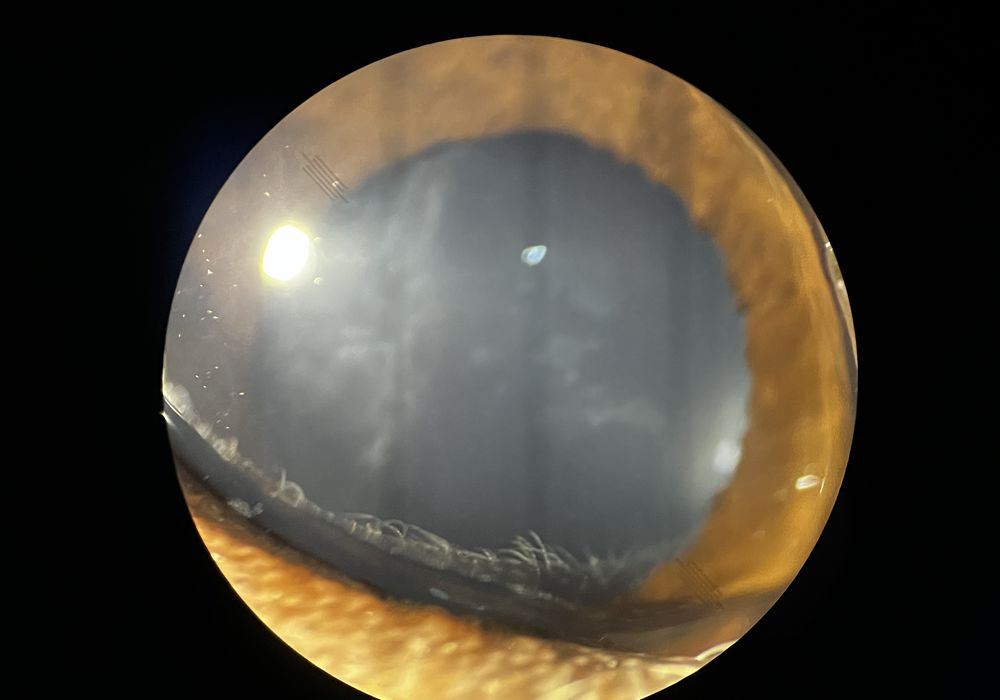

まさか これは、小夏はどうなんだと眼を見たところ、これまた、ショックの極地。未熟白内障の前期くらいのものが。

ワンちゃんだと5、6歳と若くして、白内障が発症するらしく、また、トイプードルは遺伝性白内障が示唆されているそうです。 ワンちゃの白内障は進行に伴い、ぶどう膜炎(水晶体起因性ぶどう膜炎)、緑内障、水晶体脱臼、網膜剥離などの合併症を生じ、視覚障害だけでなく 痛みを伴う状況になってしまいます。

どこまで効果があるか分かりませんが 対処療法として、白内障用の点眼薬と 水晶体に良いというサプリメントを投与しています。進行を少しでも抑えるいう治療となっています。未熟白内障後期から 成熟白内障まで 進行するようなら、手術を視野に入れないといけませんね。 目が見えなくなるって 辛いし、また、疼痛があるのも、かわいそうですし。